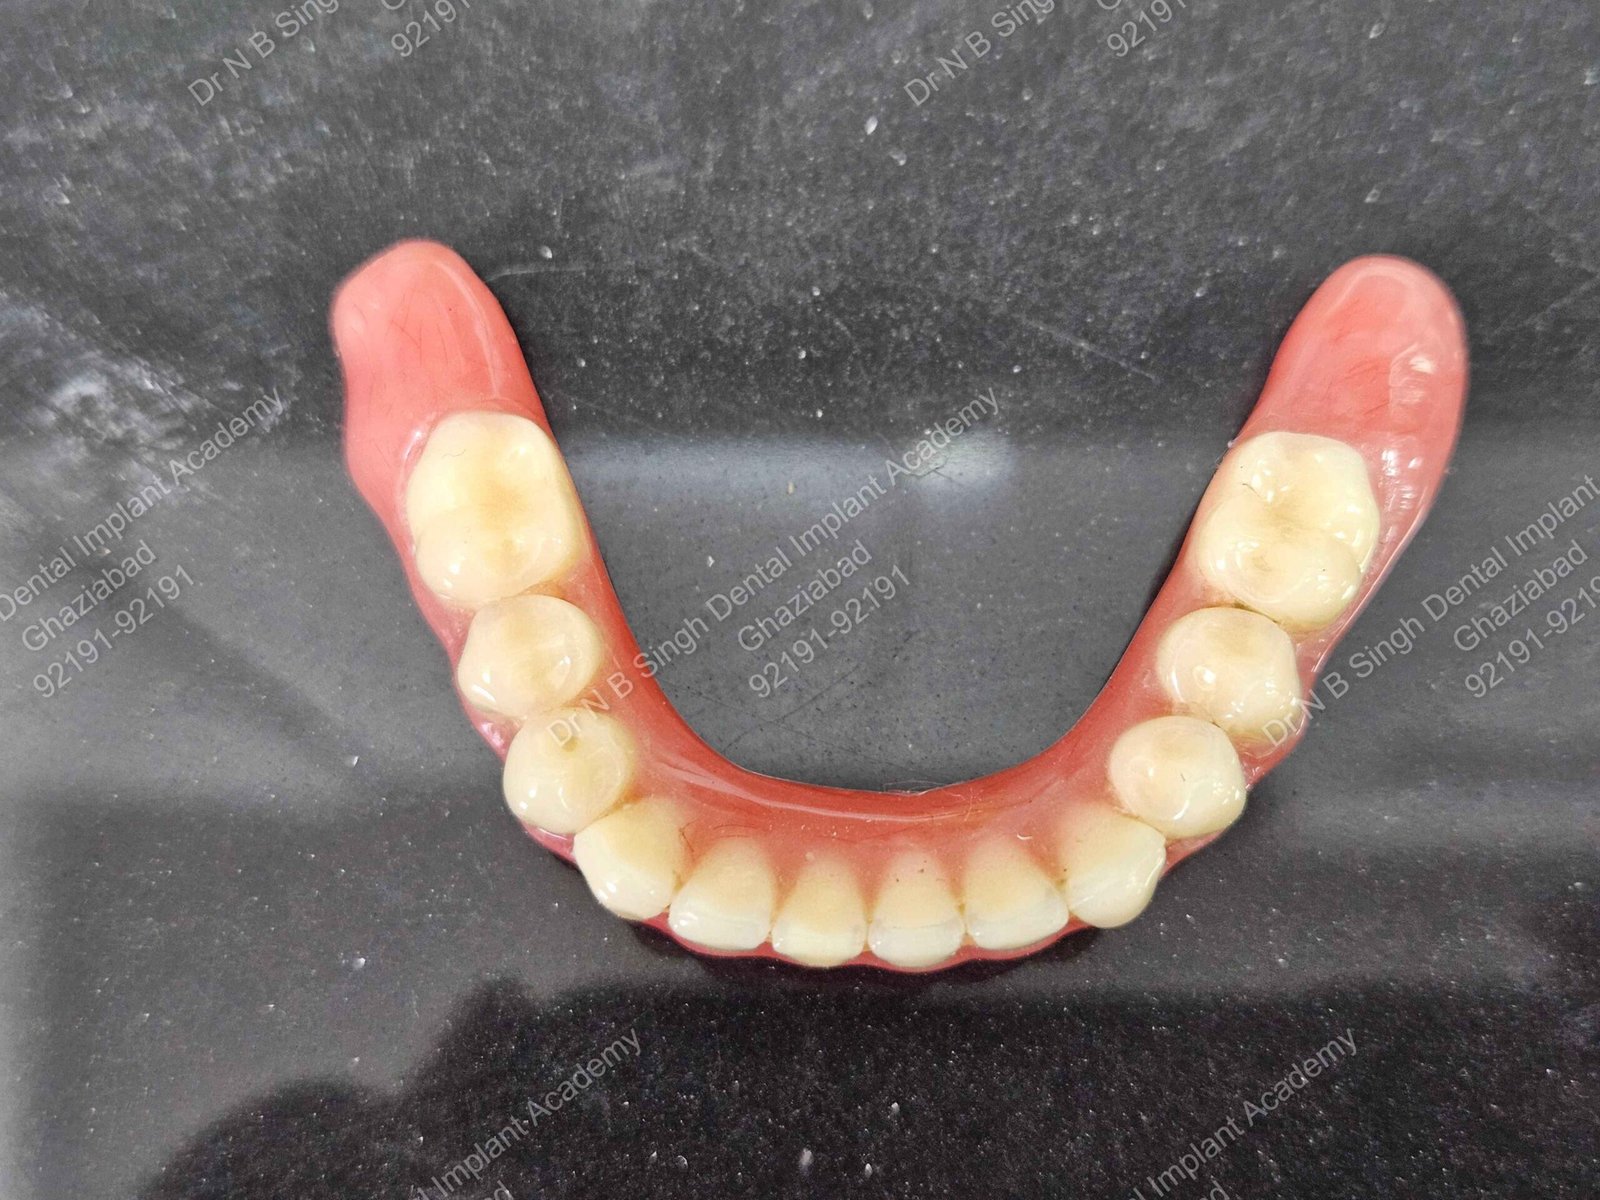

C1005 zygomatic basal implant full mouth – Ali Hasan 4

Dr. N.B. Singh